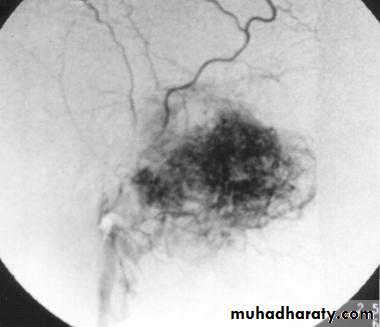

4- angiography: shows a vascular blush in the nasopharynx and is useful to determine the feeding vessel

Biopsy is contraindicated

Mainly surgical: At least 3 units of blood should be preparedThere are different techniques used preoperatively to reduce the tumor size and vascularity:

3- Embolization